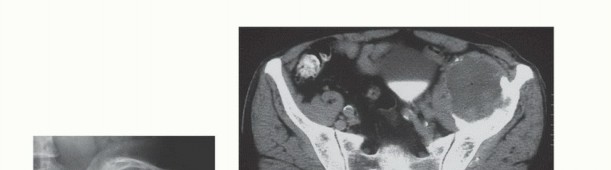

- التصوير المقطعي المحوسب (CT Scan): يوفر صورًا مقطعية مفصلة للعظام والأنسجة الرخوة، ويساعد في تحديد حجم الورم، مدى انتشاره داخل العظم، وعلاقته بالهياكل المحيطة.

- التصوير بالرنين المغناطيسي (MRI): يُعد الأداة الأكثر حساسية لتقييم الأنسجة الرخوة ونخاع العظم، ويكشف عن النقائل في مراحلها المبكرة، ويحدد مدى انتشار الورم في القناة الشوكية أو الأعصاب.